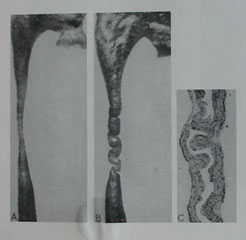

A. leszűkítése ureter csökkentésével a belső áramlási csatorna (Intrinsic) (szegmentális diszplázia, vr.stenoz) (1. ábra).

1. ábra restrikciós ureter csökkentésével a belső áramlási csatorna (Intrinsic)

B. Stephens (1980) kimutatta, a szárny keresztirányú redők nyálkahártya ureter akadályozó mennyiségű vizelet.